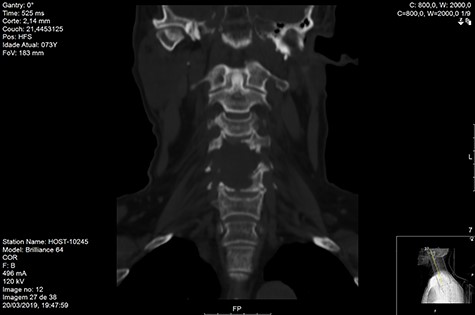

Computed tomography (CT) (Figs 1–3) and magnetic resonance imaging (MRI) (Figs 4–6) of the cervical spine were performed and revealed a lytic lesion involving most of C4, C5 and C6 vertebral bodies with bilateral extension to the posterior spinal elements of C4 and C5 and complete disruption of C4-C5 and C5-C6 intervertebral discs.

The Spinal Instability Neoplastic Score (SINS) [4, 6, 7] for assessing spinal instability from metastatic disease was used and the lesion was deemed unstable (SINS 13), with impending risk of increased neurological damage.

Findings from laboratory tests (serum protein electrophoresis) led to the diagnosis of MM. The patient was placed on a Philadelphia c-spine collar and underwent local 3D external-beam radiotherapy (20Gy in five fractions).